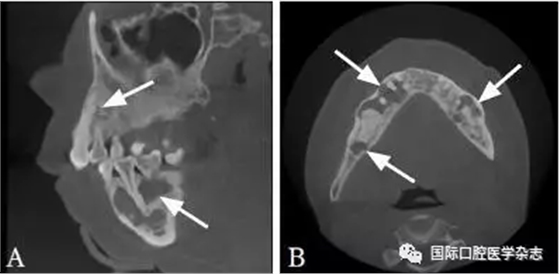

典型病例6 患者的CBCT圖像顯示上下頜骨多發(fā)性的低密度透射區(qū),但牙根完整,未見明顯吸收,牙齒仍有活力(圖6)。

A:矢狀位;B:水平位。

圖 6 骨結(jié)構(gòu)不良的CBCT圖像

Fig 6 CBCT of osseous dysplasia